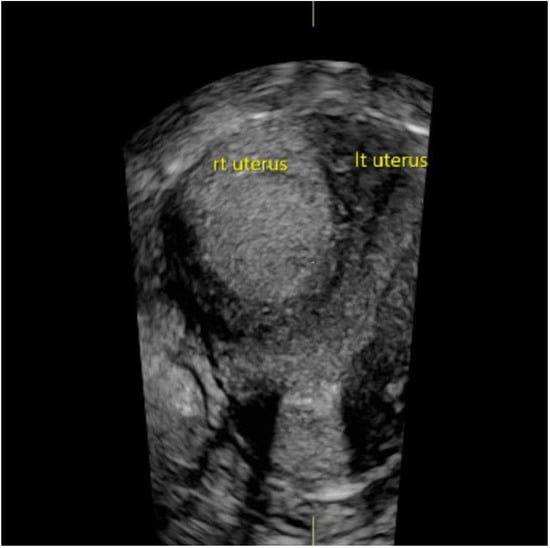

Results and Discussion: A healthy 9 year old girl was referred to our outpatient clinic of Pediatric Gynecology because of vaginal bleeding since two months, without trauma and accompanied by mild abdominal discomfort. She suffered from daily vaginal bleeding, varying from spotting to small blood clots. No vaginal discharge, pruritus, fever or constipation. She did not use medication. Physical examination showed a 1.29 m height girl, weighing 28 kg with Tanner stage 1. Genital examination showed normal prepubertal external genitalia without skin lesions or vaginal discharge. A vulvovaginal sample for bacterial culture was normal. Abdominal ultrasound showed an enlarged uterus with a 2.2 cm hyperechogenic intracavitary mass without blood flow (Figure 1) and normal ovaries. It was concluded to be hematometra. MRI confirmed normal development of internal genitals and hematometra. Blood results were (repeatedly): Hb 7.0 mmol/L; FSH 0.7 IU/L; LH < 0.1 IU/L; estradiol < 20 pml/L. Normal values of infection markers, tumor markers, thyroid function and testosterone. Hysteroscopy was performed under general anesthesia and showed a round, pale pedunculated intracavitary structure. Biopsies showed a thrombus, without signs of malignancy. In a following hysteroscopy the structure was completely removed without significant blood loss. The pathology report showed a benign capillary-venous malformation.

Figure 1.

Abdominal ultrasound.